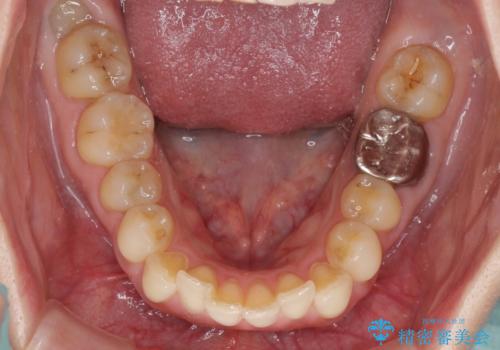

- 上下の前歯のデコボコを気にして来院された患者様です。

妊娠中であり、途中通院が難しくなる可能性があることから、インビザラインによる矯正治療を行うこととしました。

上下顎歯列全体の後方移動とIPR(歯と歯の間を削る)によってデコボコが解消するように設計しました。